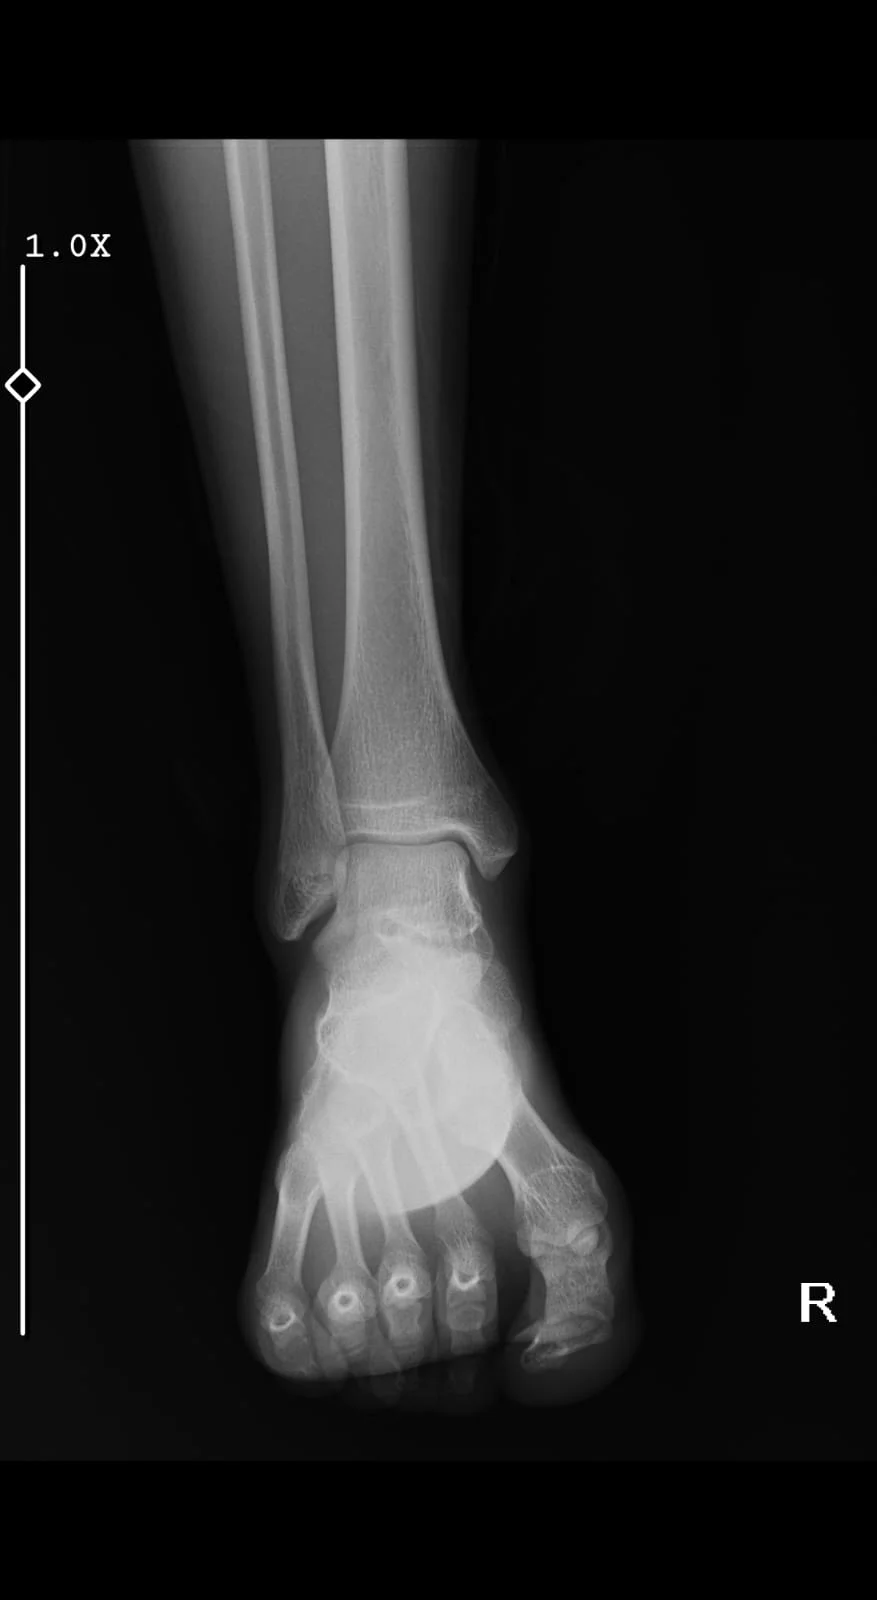

Doktor bilekte çatlak olduğunu söyledi hangi kemikte olduğunu merak ediyorum bilenler yorumlayabilir mi?

Paylaştığınız röntgen görüntüsü sağ ayak bileği ve ayağın ön-arka (AP) görünümünü göstermektedir.

Bir röntgen görüntüsü üzerinden kesin tanı koymak, özellikle de küçük çatlakları (fissür) tespit etmek uzmanlık gerektirir. Ancak bu görüntüde dikkat çeken bir bölge bulunmaktadır:

Görüntüde sağ fibula (serçe parmağı tarafındaki ince kemik) alt ucunda (dış mallevol), eklem hattına yakın bir bölgede bir düzensizlik veya hat göze çarpmaktadır. Bu durum bir kırık veya çatlak belirtisi olabilir.

Radyoloji Raporu: Röntgenler tek bir açıdan yeterli olmayabilir. Genellikle yan ve çapraz görüntülerle birlikte değerlendirilir. Kesin sonuç için radyoloji uzmanının hazırladığı raporu incelemeniz en doğrusudur.